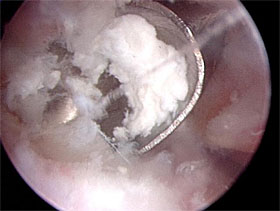

Die Kalkablagerungen werden im Rahmen der Arthroskopie

eröffnet und entleert, also ausgeräumt.

Das Kalkdepot wird im Rahmen der Arthroskopie eröffnet

und dann durch Einbringung eines kleinen Löffels schrittweise

entfernt. |